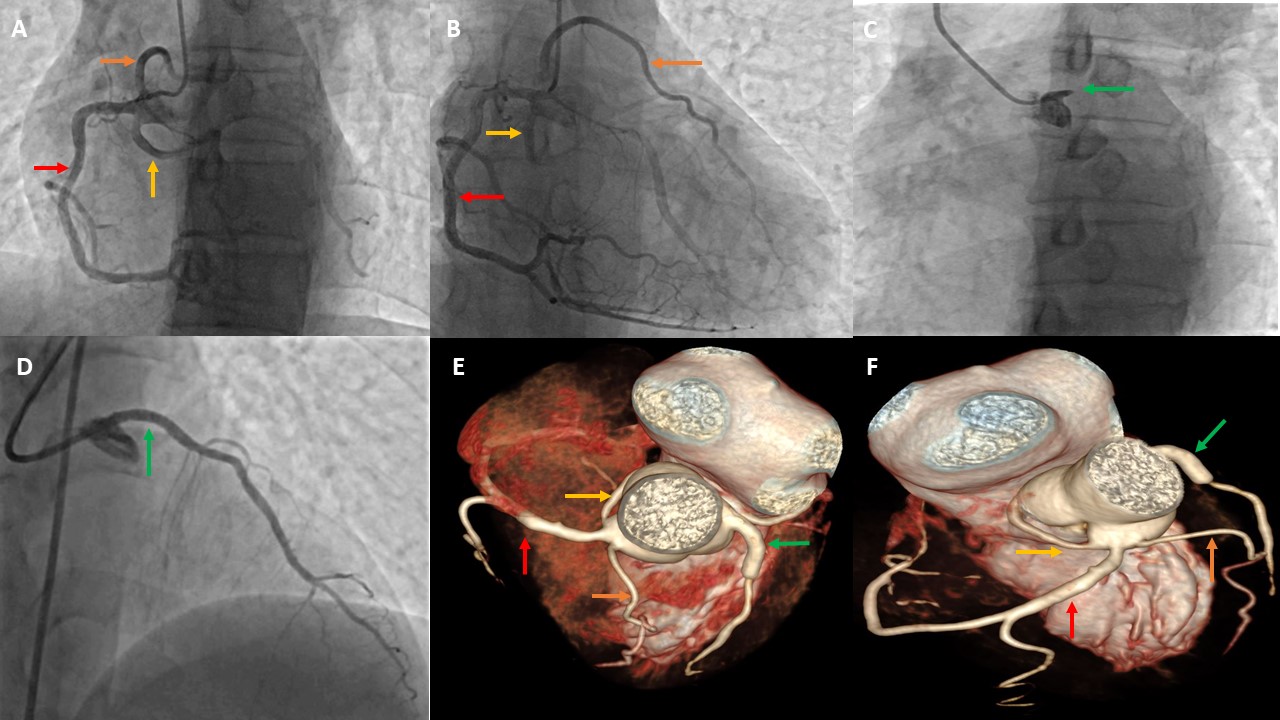

Complex Coronary Angiography in Jaipur – Dr. Anil Kumar Choudhary If you're suffering from chest pain, breathlessness, or have been diagnosed with multiple or difficult heart blockages, Complex Coronary Angiography is the first and most crucial step in your treatment journey. Dr. Anil Kumar Choudhary, the best interventional cardiologist in Jaipur, offers expert-level precision in performing this life-saving diagnostic procedure. With vast experience in advanced cardiac imaging and diagnosis, Dr. Choudhary provides highly accurate and detailed coronary assessments, especially in patients with multiple blockages, previous bypass surgeries, diabetes, or high-risk profiles. 🩺 What is Complex Coronary Angiography? Coronary Angiography is a diagnostic procedure that uses a special contrast dye and X-ray imaging to visualize the arteries supplying blood to your heart. In complex cases, this procedure is performed with advanced imaging techniques and requires high-level expertise to interpret intricate blockages or anomalies. Complex Coronary Angiography is typically needed when: There is suspected multi-vessel disease The patient has chronic total occlusions (CTOs) There’s history of previous stents or bypass surgery (CABG) The patient has diabetes, kidney disease, or low ejection fraction (LVEF) Symptoms are unusual, prolonged, or high risk 🔬 Dr. Anil Kumar Choudhary’s Expertise in Complex Angiography Dr. Choudhary is known for his high diagnostic accuracy and sharp interpretation of even the most challenging coronary cases. His use of intravascular imaging tools such as: IVUS (Intravascular Ultrasound) OCT (Optical Coherence Tomography) FFR (Fractional Flow Reserve) ensures detailed visualization and functional analysis of blockages. This level of precision helps in planning the most appropriate and safe intervention, whether it be angioplasty, stenting, or surgery. 💡 Benefits of Choosing Dr. Anil Kumar Choudhary for Complex Coronary Angiography 🏥 Advanced Cath Lab with high-resolution imaging systems 🎓 Expert in diagnosing complex coronary artery disease (CAD) 🧠 Deep understanding of hemodynamics and coronary physiology 💯 Helps avoid unnecessary stenting through accurate lesion assessment 🩺 Specialist in post-bypass and restenosis case evaluation ✅ When is Complex Coronary Angiography Recommended? Recurrent chest pain or angina despite medication Suspicion of triple vessel disease or left main artery blockage Previous CABG (bypass surgery) or angioplasty patients Cases with diabetes, chronic kidney disease, or heart failure Prior equivocal stress test or CT angiography results Evaluation of in-stent restenosis or stent failure ❤️ Why Dr. Anil Kumar Choudhary is the Best Cardiologist for Complex Angiography in Jaipur 👨‍⚕️ Over a decade of interventional cardiology experience 💻 Use of cutting-edge technology and imaging tools 🧪 Expertise in high-risk and redo cases 🤝 Patient-centric care with ethical and transparent consultation 📈 High diagnostic precision ensuring targeted treatment planning 📍 Visit Jaipur’s Best Coronary Angiography Specialist Today Don't leave your heart health to chance. If you or your loved one has symptoms of serious heart disease or complex cardiac history, trust Dr. Anil Kumar Choudhary, the most reliable name for complex coronary angiography in Jaipur.

Complex Coronary Angioplasty in Jaipur – Dr. Anil Kumar Choudhary When it comes to advanced and life-saving cardiac interventions, Dr. Anil Kumar Choudhary is widely recognized as the best interventional cardiologist in Jaipur, known for his exceptional skill in performing Complex Coronary Angioplasty. Specializing in treating high-risk and difficult coronary blockages, Dr. Choudhary delivers world-class results using the latest technology and techniques. ❤️ What is Complex Coronary Angioplasty? Complex Coronary Angioplasty (also known as PCI – Percutaneous Coronary Intervention) refers to advanced angioplasty procedures used to treat challenging coronary artery blockages. These may include: Chronic Total Occlusions (CTOs) Left Main Coronary Artery Disease Severe Multivessel Coronary Artery Disease Calcified Arteries Bifurcation Lesions Restenosis (re-blockage after stenting) Unlike routine angioplasty, these cases demand high expertise, specialized tools (like rotablation, IVUS, OCT), and a deep understanding of coronary anatomy and hemodynamics. 🏥 Dr. Anil Kumar Choudhary’s Expertise in Complex PCI With a reputation for excellence in interventional cardiology, Dr. Anil Kumar Choudhary has handled some of the most complex coronary cases with successful outcomes. His approach combines: Precision and safety Use of advanced imaging (IVUS/OCT) for lesion assessment Rotablation & atherectomy for hard, calcified plaques Bifurcation and multivessel stenting techniques Experience in left main coronary angioplasty 🚨 When is Complex Angioplasty Recommended? Dr. Choudhary may suggest complex angioplasty in cases such as: Patient is not suitable for bypass surgery (CABG) High-risk or elderly patients with multiple blockages Blockages in critical arteries like the left main artery Patients with diabetes or weak heart function (low ejection fraction) Previously failed angioplasty or re-narrowing of stents 🔬 Advanced Tools & Techniques Used by Dr. Choudhary IVUS (Intravascular Ultrasound) – for accurate visualization inside arteries OCT (Optical Coherence Tomography) – to guide precise stent placement Rotablation – for drilling hard, calcified plaques Dual-stenting techniques – for complex bifurcation lesions Drug-eluting stents (DES) – to reduce re-blockage risk ✅ Why Choose Dr. Anil Kumar Choudhary for Complex Coronary Angioplasty in Jaipur? 🩺 Over a decade of experience in complex and high-risk PCI 🏥 Advanced Cath Lab with cutting-edge imaging tools 💯 High success rate in critical cases 👨‍⚕️ Personalized treatment planning and post-procedure care 💬 Transparent patient communication and ethical practice Recognized as the best cardiologist in Jaipur for complex interventions ❤️ Conditions Treated with Complex Angioplasty Chronic Total Occlusion (CTO) Triple Vessel Disease Left Main Coronary Artery Blockage Coronary Artery Calcification Bifurcation and Trifurcation Lesions Stent Restenosis Low LVEF with CAD Unstable Angina or Heart Attack 📍 Visit the Best Heart Specialist in Jaipur for Complex Coronary Care If you've been advised bypass surgery or have been diagnosed with multiple or complex blockages, consult Dr. Anil Kumar Choudhary for a second opinion. Many patients have avoided open-heart surgery through his expert complex angioplasty.